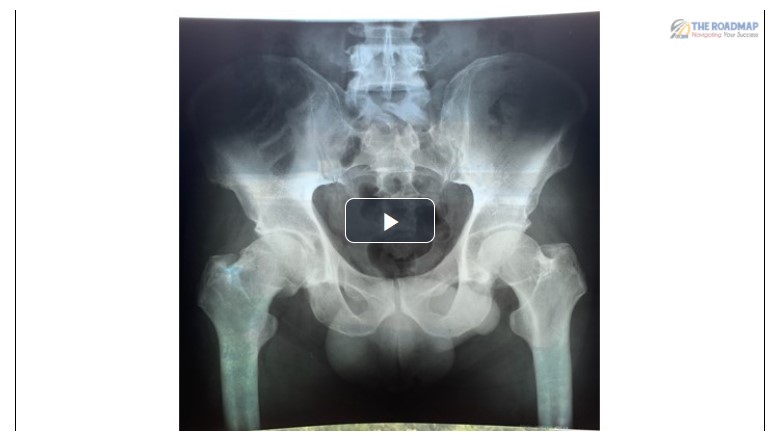

• 3 site Hip Injection + L-3-Exam - Dennis Harper DC

Movie + 2 extras

Dr. Harper performs a brief Hip & L-3 exam and demonstrates 4 different injections to support a chronic longstanding degenerative hip as shown on X-Ray (included)